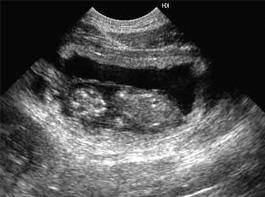

Первые признаки того, что беременность у кошки наступила, начинают появляться примерно на 3 неделю после оплодотворения – увеличение веса и аппетита, увеличение размеров и усиление розовой окраски сосков. До этого времени животное часто бывает наоборот, менее активно, аппетит и активность могут быть снижены, что часто приводит владельцев к ложным выводам о возможном заболевании. Начиная с 2-3 недельного срока беременность кошки можно подтвердить по УЗИ.

На 4-6 неделю при пальпации уже определяются плоды, однако самостоятельно пальпировать брюшную полость беременной кошки нежелательно – неосторожные движения могут привести к выкидышу. На 6-й неделе у беременной кошки уже хорошо заметен округлившийся живот. К 7-й неделе можно уже наблюдать шевеление плодов, увеличиваются молочные железы, иногда можно наблюдать небольшое количество выделений молочного цвета из влагалища.

Для кормления беременной кошки нужно применять специальные корма для беременных, правильное кормление поможет хорошо развиваться будущим котятам. За 3-4 дня до родов желательно сделать УЗИ, для определения количества и размеров плодов – это поможет спрогнозировать течение беременности (иногда котята бывают слишком крупные – в таком случае решается вопрос об операции).